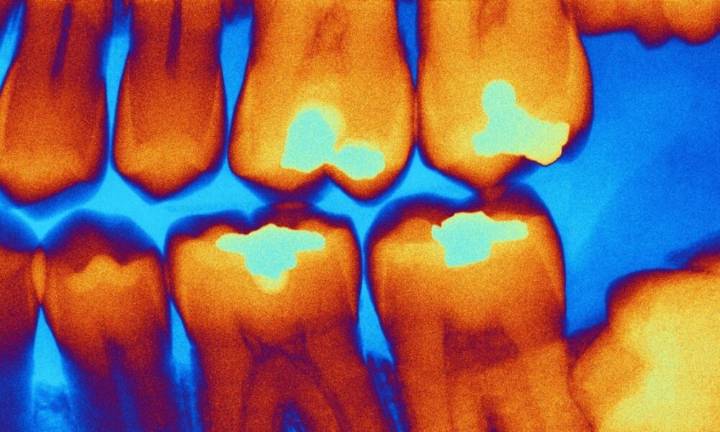

Uno de los mayores retos en el tratamiento de las caries, según explicó la institución, es distinguir la dentina infectada por caries , que debe retirarse, de la dentina dañada pero aún viable, para su conservación.

Subraya que el nuevo aparato evita estos inconvenientes gracias a un método no invasivo basado en una sonda óptica que